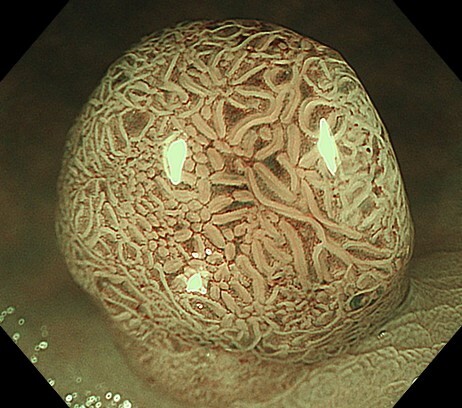

健診:PET-CT、MRI/MRA、胃内視鏡、大腸内視鏡

午前中に胃・大腸内視鏡を行い、午後にFDG-PET/CTを受ける1日完結プランです。PETを含むため、前日または当日の朝にホテルで下剤を服用します。内視鏡で消化管を精査しつつ、PETで全身のがんリスクを可視化できます。特に早期がん、転移、隠れた腫瘍の発見に有効で、全身を網羅的に評価したい方に適しています。

NEO HEALTHCAREは、大阪本町に位置する内視鏡専門クリニックです。 世界トップレベルの内視鏡技術とオリンパス社製の最新内視鏡機器により、最高水準の医療と快適な環境を提供します。

胃または大腸の内視鏡を鎮静下で行い、がん・ポリープ・炎症を精密評価する基本プラン。早期発見を重視し、必要に応じて生検やポリープ切除を追加実施します。

上下部内視鏡検査と全身の超音波検査(頸動脈・心臓・乳腺・腹部・甲状腺)を組み合わせ、消化管から主要臓器までを網羅的に評価する高精度健診プログラムです。

内視鏡に加え、全身のがんを詳細に調べるプレミアムPET/CTを組み合わせた総合がん検査。頭部MRI/MRAや胸部CTなどを含み、主要臓器を一度で網羅的に評価します。